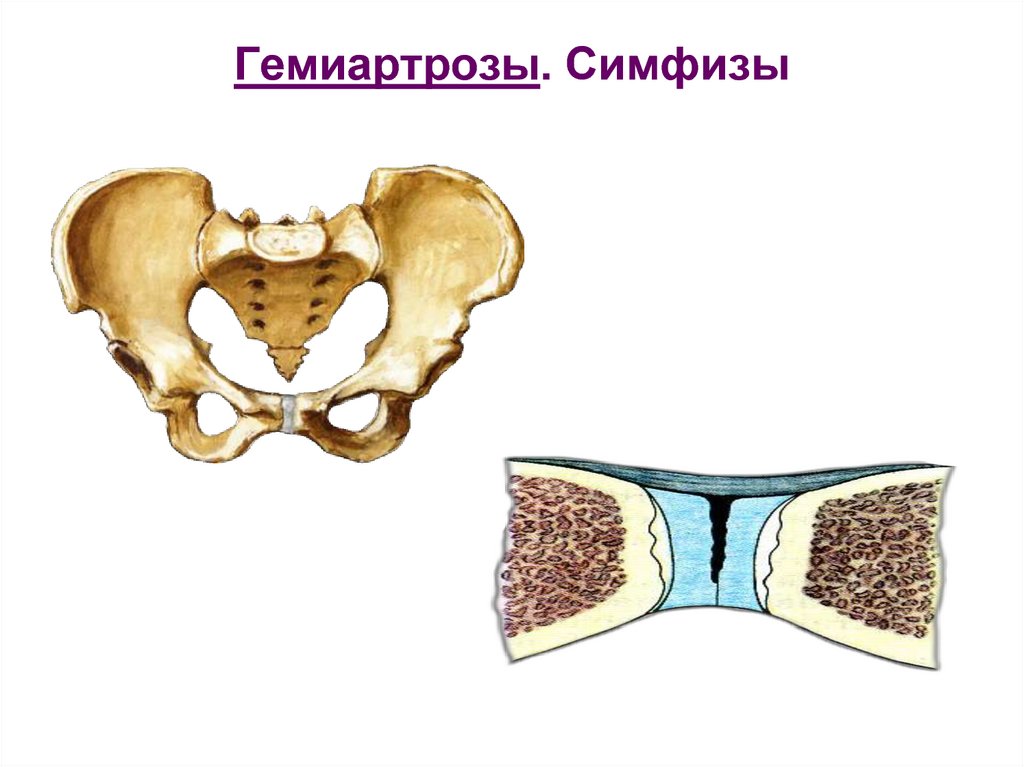

Структура и анатомия синдесмоза: научные иллюстрации